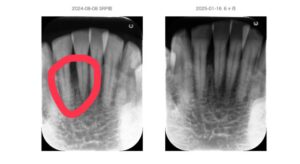

【症例例】咬合管理で安定したケース

50代 性別 男性

前歯に6mmの歯周ポケットと動揺あり。

歯周基本治療と咬合調整後

再生療法併用。

3ヶ月後にはポケットは3〜4mmに改善し、現在も安定しています。

Before:

北新地での歯周病治療前の口腔内写真|歯ぐきの腫れと炎症が見られる状態

After:

北新地での歯周病治療後の口腔内写真|炎症が改善し歯周組織が安定した状態